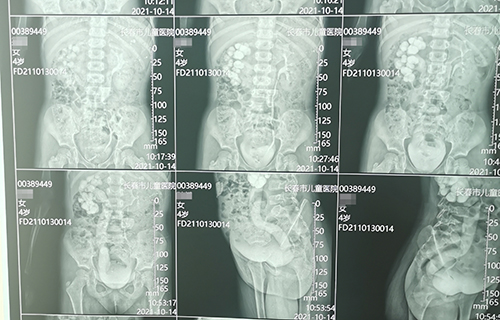

长春4岁女宝佳佳(化名)间歇性腹痛1个月,诊断为输尿管末端狭窄。这种病在儿童中发病率仅为5‰,但危害却不容小觑,长期发展会导致患侧泌尿系扩张积水,影响肾功能甚至导致肾衰竭。故一旦确诊需尽早手术治疗。那么,佳佳到底怎样了呢?

术前准备完毕。10月15日,栾志勇主任、谢方达副主任为佳佳行输尿管远端狭窄微创手术,在其肚脐周围打了3个直径5mm的小孔,在腹腔镜下顺利实施了输尿管膀胱再植。手术用时仅为3小时,出血量也比较少。

佳佳复查彩超,手术效果良好,达到出院标准。10月22日,佳佳就可以回家了。截止到目前,此类微创手术已完成8例。